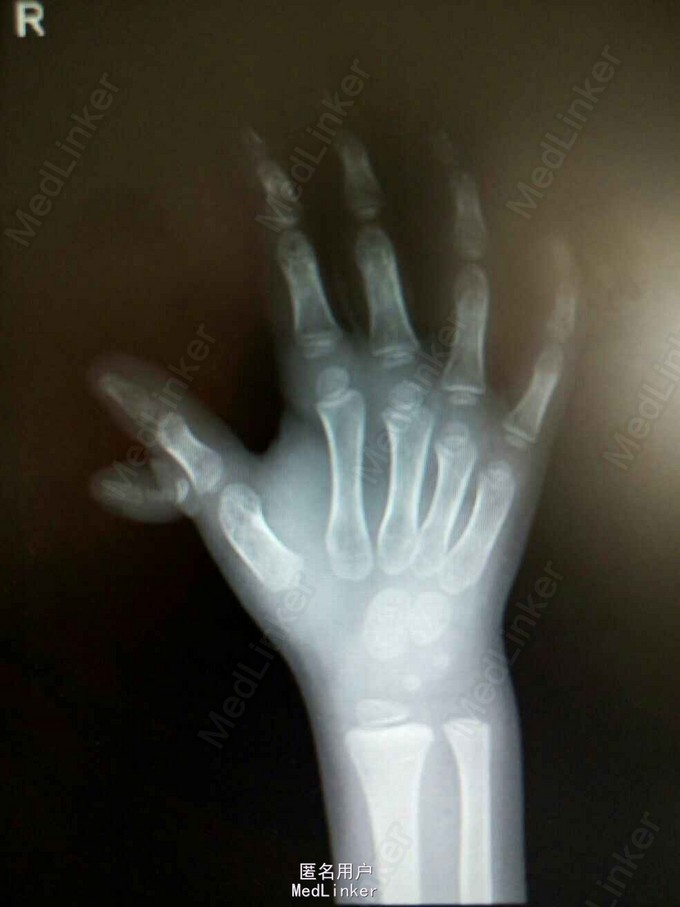

查体:右手拇指多指畸形,自右手拇指近节中部,向外侧生发出一拇指节,活动可,未触及粘连,触之无压痛,表面皮肤未见明显红肿。辅助检查:右手正斜位X光检查提示:右侧拇指多指畸形,与正常拇指无骨性连接,余右手各掌骨、指骨、腕骨形态以及骨质未见异常。各指间关节、掌指关节以及腕关节结构关系正常,关节面光滑,关节间隙无变窄。

诊断:右手拇指多指畸形 处理:全麻下行多指切除术